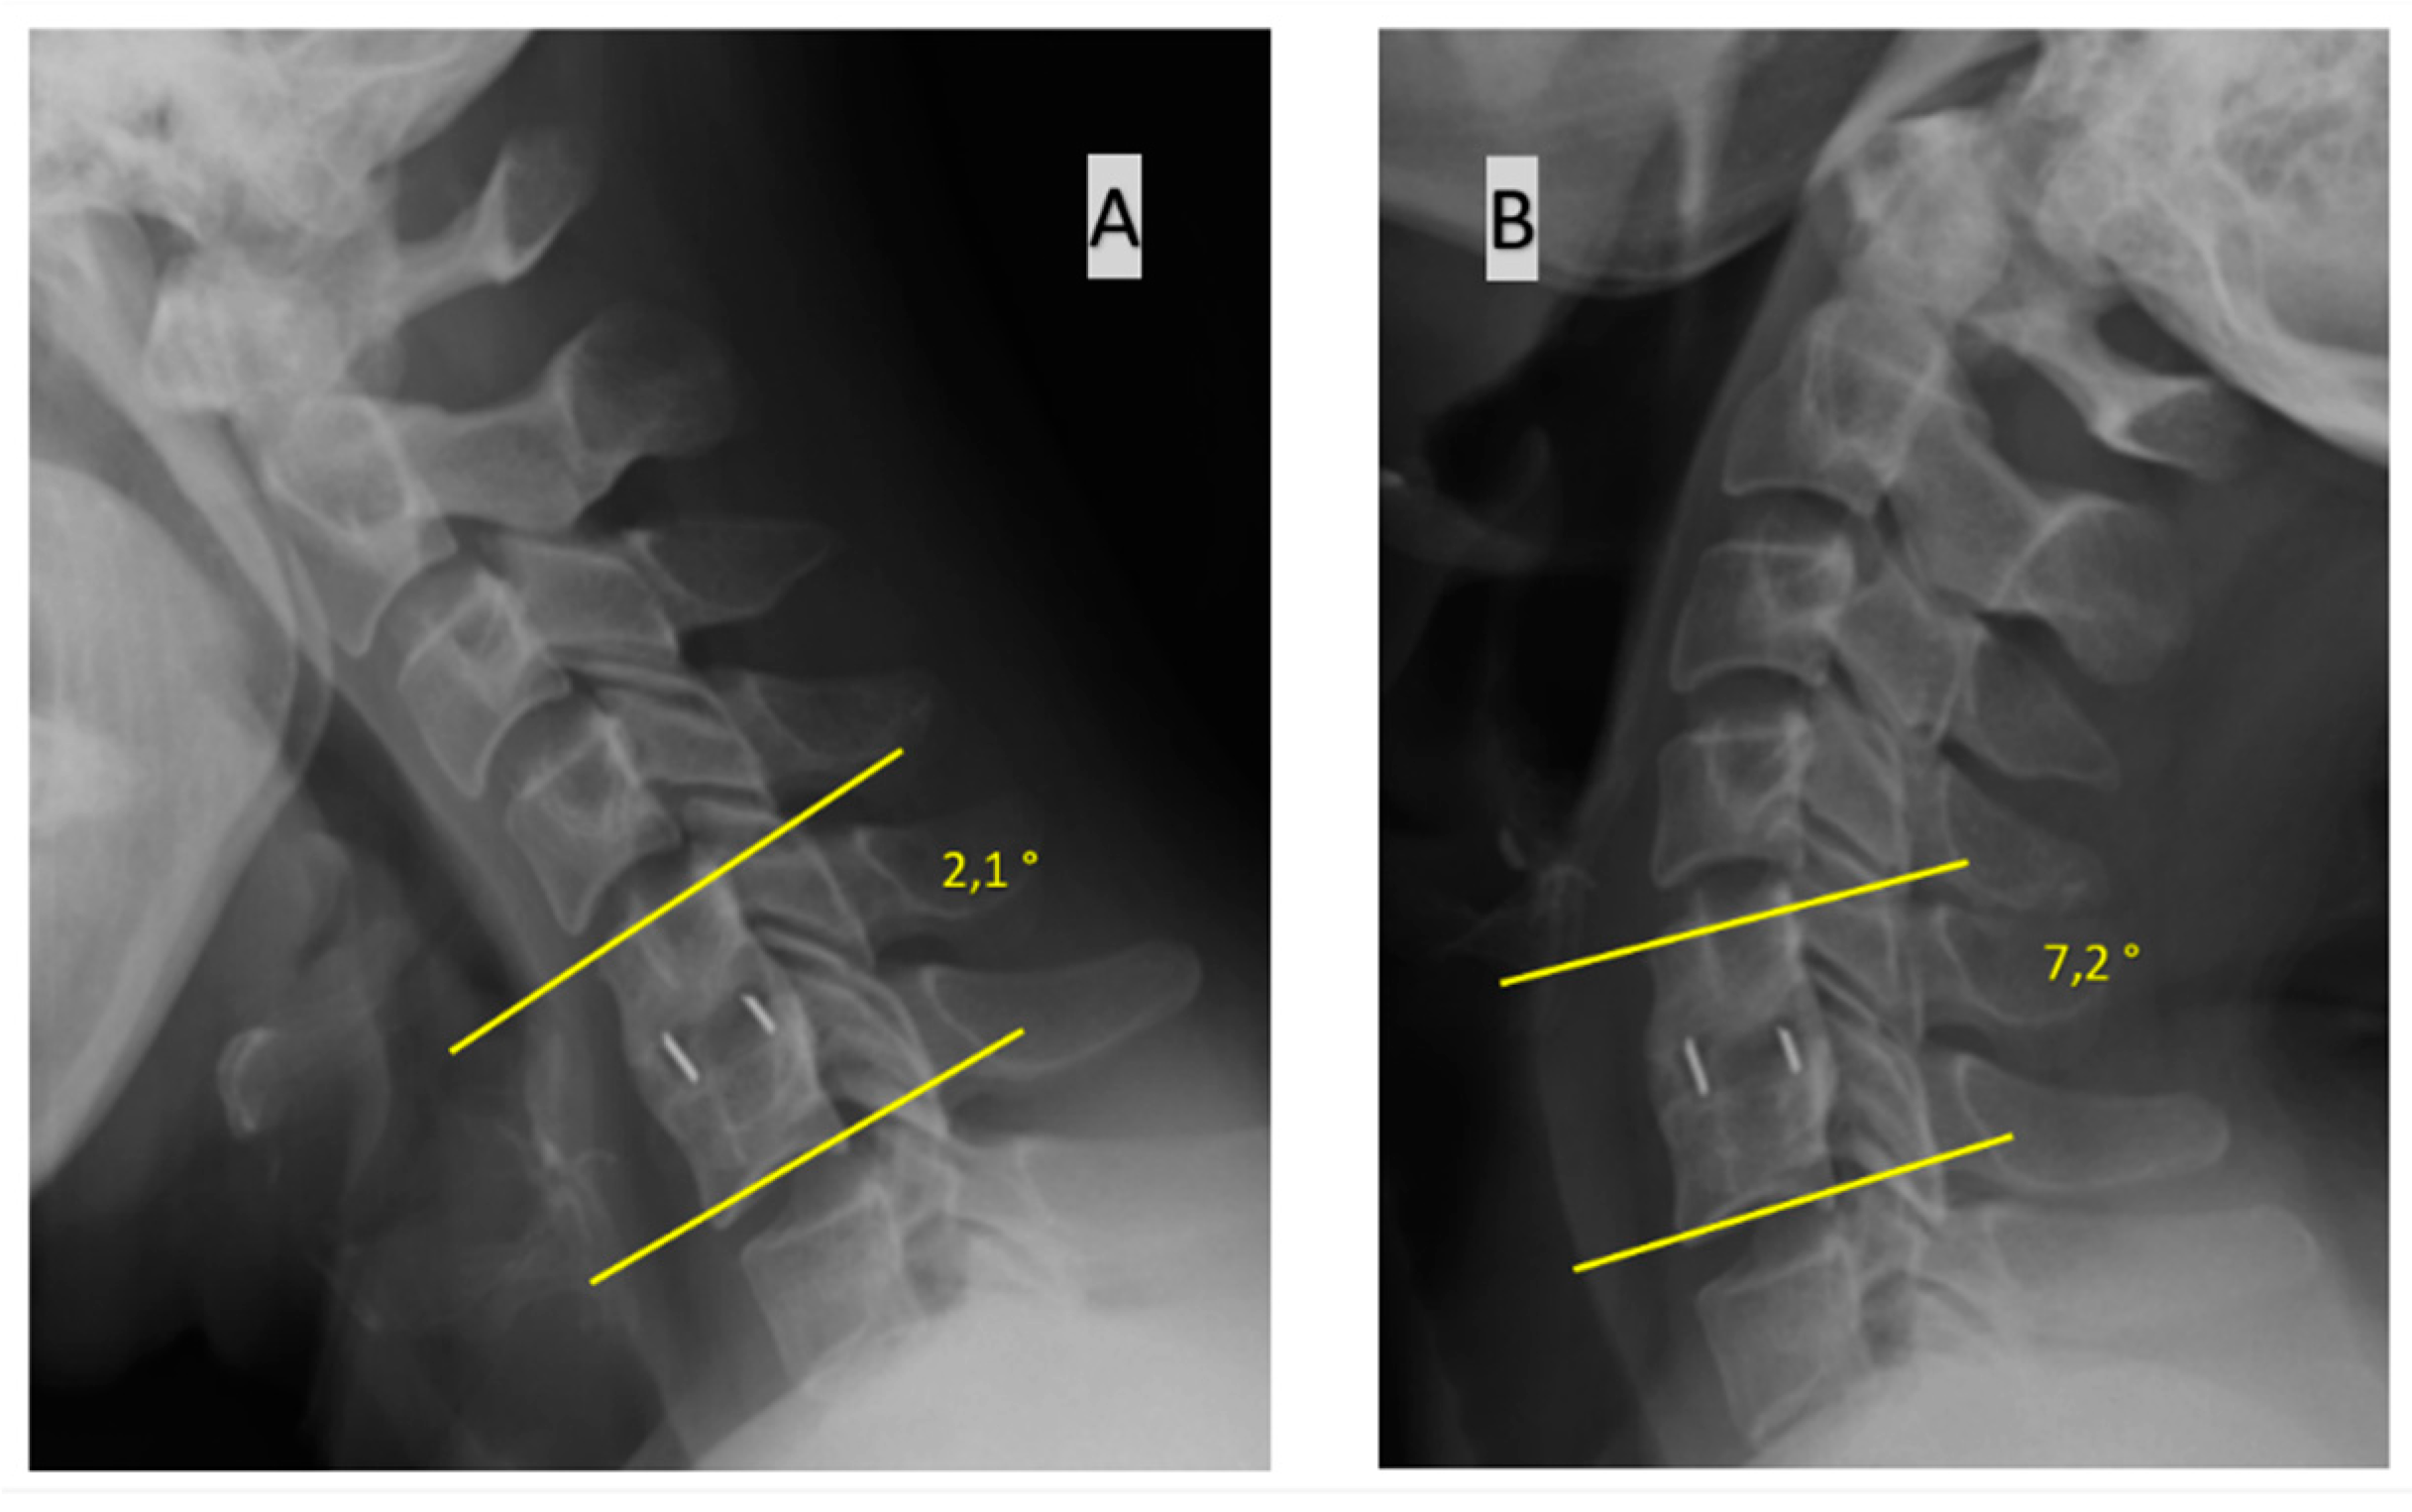

From www.mdpi.com

JPM Free FullText SingleLevel Anterior Cervical Discectomy and Interbody Fusion A Cervical Fusion Reddit Anterior cervical discectomy and fusion (acdf) surgery is a type of surgical procedure that is performed to relieve pressure. Despite the risks involved, many patients see positive results. Reversal of the normal cervical lordosis. So it looks like i may be headed for a cervical fusion after discovering disc disease and cci throughout my neck due to eds. Persistent neck. Cervical Fusion Reddit.

JCM Free FullText Reliability and Utility of Various Methods for Evaluation of Bone Union Cervical Fusion Reddit Over the past 15 years, numerous studies have come out demonstrating the benefits of cervical disc replacement over the “gold standard” of anterior cervical discectomy and. Anterior cervical discectomy and fusion (acdf) is a type of neck surgery that involves removing a damaged disc to relieve spinal cord or nerve root pressure and alleviate corresponding pain,. Reversal of the normal. Cervical Fusion Reddit.